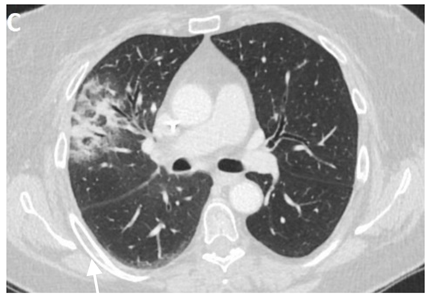

6.4.2. Chest CT-Scan

In the event of worsening symptoms after empirical antibiotics, Chest CT may provide more insights. Interestingly, the opacification lines in both X-ray and CT conform to radiation port rather than anatomical lines of lung structure, which could be diagnostic. Identified progression outside the lung field might suggest immune-mediated lymphocytic alveolitis [72]. Various stages of presentation provide different imaging outlooks (Table 3).

Computed Tomography (CT) chest illustrating post-radiation therapy changes in the lungs.

During the acute exudative stage, features of ground-glass attenuation or homogeneous consolidation may be noticed. A patchy consolidation that confirms the irradiation portal is also suggestive of the early phase. A discrete consolidation that conforms to the shape of the irradiation portal is proliferative changes of irradiation [71].

A chronic fibrosis stage with features of parenchymal distortion, traction bronchiectasis, and pleural thickening resulting in volume loss and irreversible changes are noticed. Refer to Table 2.